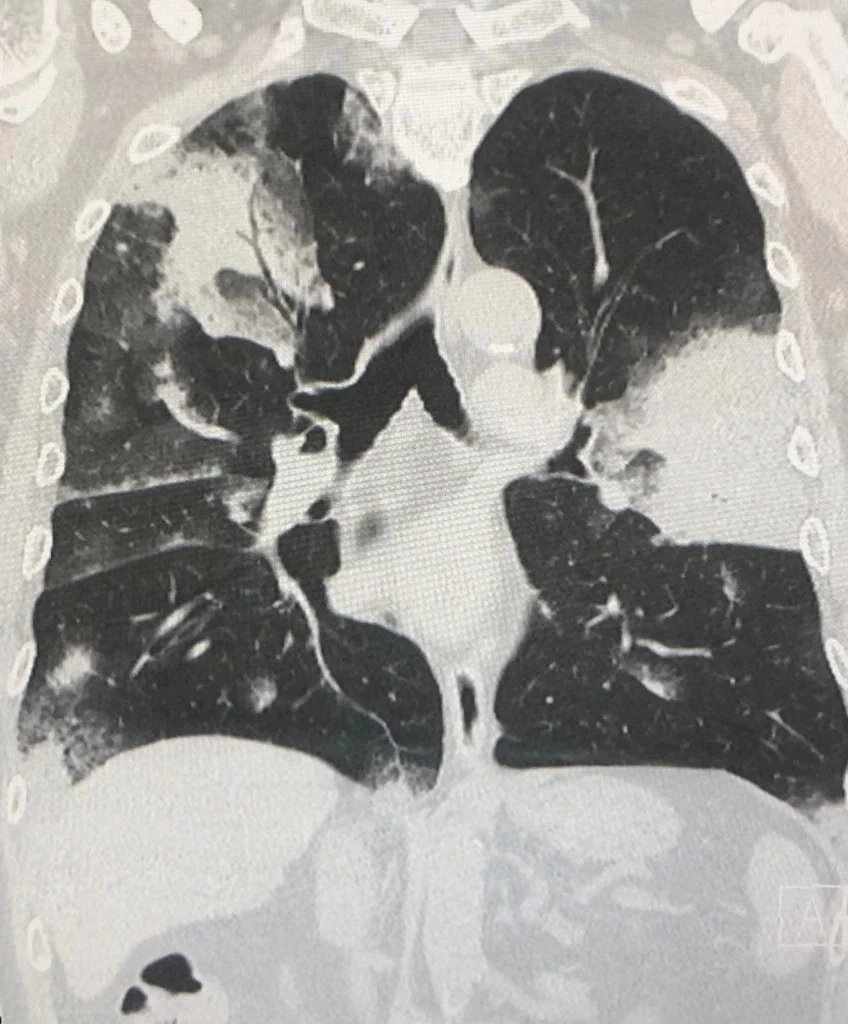

ตรวจร่างกาย ผอมลง เอกซเรย์ปอดมีฝ้าขาวทั้ง 2 ข้าง (ดูรูป) เอกซเรย์ปอดครั้งก่อนวันที่ 18 กุมภาพันธ์ 2563 ปกติ (ดูรูป) ทำคอมพิวเตอร์ปอดเห็นฝ้าขาวทั้งปอดซ้ายและปอดขวา (ดูรูป) ค่ามะเร็ง CEA ในเลือดสูง 7.4 เจาะชิ้นเนื้อจากปอดด้านซ้าย ส่งตรวจไม่พบเชื้อวัณโรค ไม่พบเชื้อรา ตรวจทางพยาธิวิทยา พบเป็นมะเร็งปอดชนิด adenocarcinoma